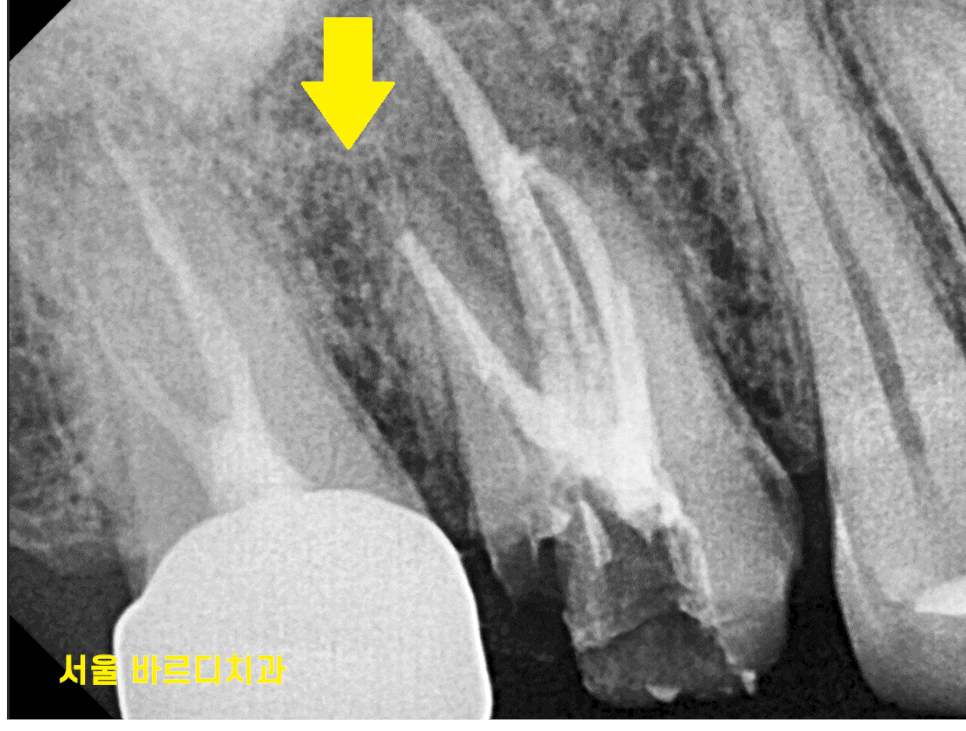

3D ct 등을 통해 정밀한 검사를 진행한 결과,

치아 뿌리 주변의 염증으로 한쪽 뼈를 녹였네요.

ct 상 한쪽 뼈만 녹아있는 상황이라

x-ray를 봐서는

염증이 없어진건지 잘 모르시겠죠~?

변화가 된 모습만 비교해드릴께요~

뿌리 절반 이상 염증들이

3달의 치료과정을 통해

손톱만큼 줄어들었습니다.

이제 뿌리 끝 까만 부분

거의 보이지 않습니다.

염증이 남아있으면 제대로 뼈가 차지 않는대요.

깨끗하게 염증이 없어졌기 때문에

까맣게 녹아 버린 뼈가

다시 하얗게 채워진 모습을 볼 수있네요~